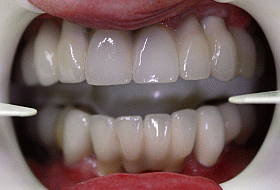

This picture shows the final result – 2 full dental bridges screwed onto implants – completing full mouth restoration with All-on-6 & All-on-4 dental implant systems.

To provide natural look to final restorations, outer bridge framework was made of pink porcelain (to imitate natural gum), which also allows for the crowns to be made to the proportion and look of natural teeth.